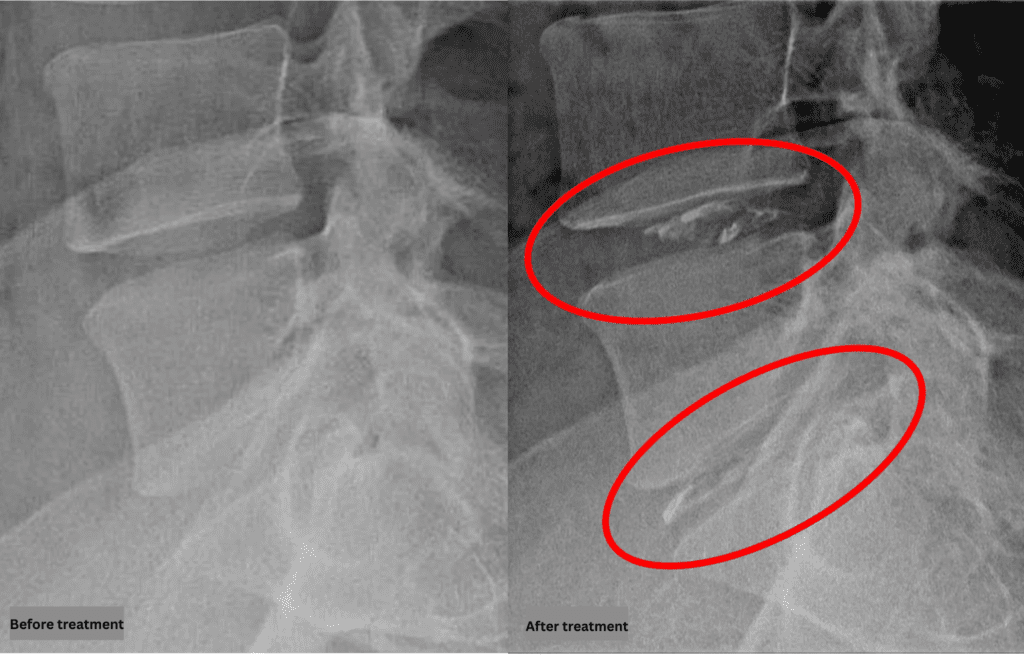

After consulting with the patient, the Cellgel Method was performed on L4/5, 5/s.

The treatment took about 25 minutes.